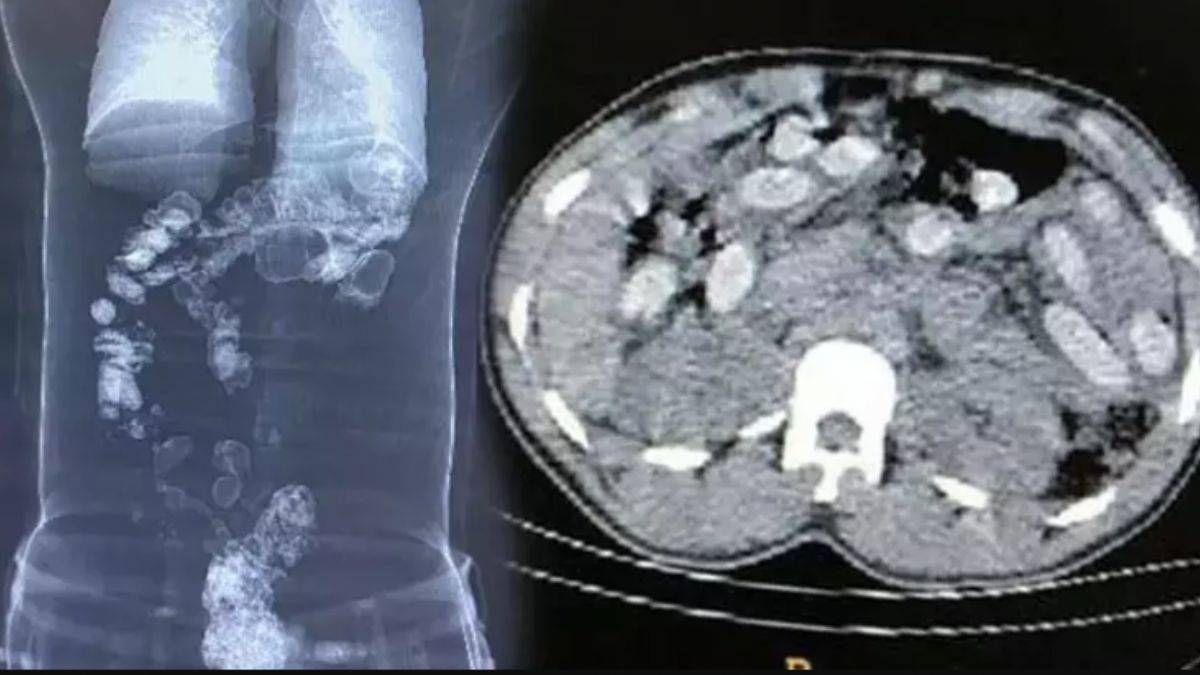

Rize'de iç çamaşırı ve bağırsaklarına gizledikleri 868 gram sentetik uyuşturucuyla yakalanan İran uyruklu 3 kadın tutuklandı.

Zanlıların iç çamaşırlarına saklanmış 9 kapsül şeklinde sentetik uyuşturucu ele geçirildi. Beden muayenesi için hastaneye götürülen şüphelilerin bağırsaklarında da 868 gram uyuşturucu bulundu.